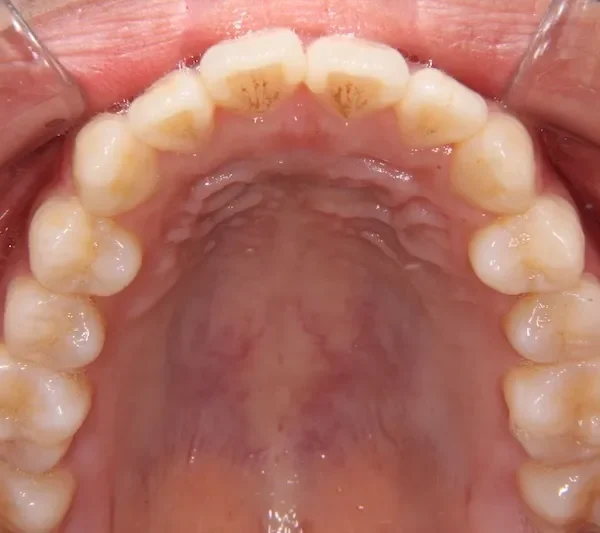

初診時

前歯で物が噛みちぎれないを主訴に来院された患者様です。

非抜歯で、オリジナルリンガルアーチと歯科矯正用アンカースクリューを用いて治療しました。

治療回数15回、1年の治療期間で矯正治療を終了しました。

主訴が改善され、ご満足頂きました。